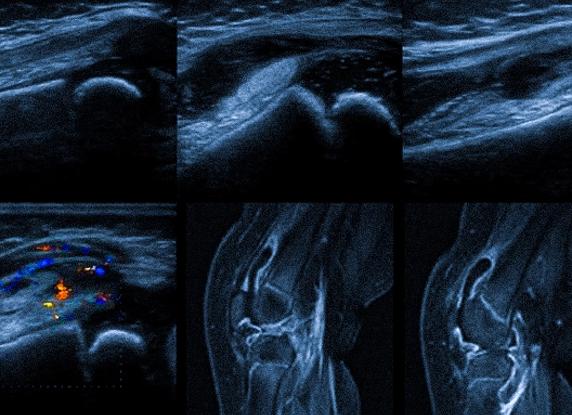

Для выявления травм мениска и мышечных спазмов может быть применено ультразвуковое исследование (УЗИ). Его проводят достаточно часто, ведь именно ультразвук максимально чувствительный способ изучения травм нижних конечностей.

Рассматривая эффективность, УЗИ коленного сустава существенно уступает магнитно-резонансной томографии, ведь она максимально чувствительна при выявлении деформации мениска. Однако во время процедуры УЗИ можно увидеть:

• текущее изменение формы хряща;

• нарушения в его контурах;

• наличие гипоэхогенной полоски на месте поражения.

Кроме этого, если будет обнаружено изменение эхогенности в контуре мениска, то это лишний раз подтвердит наличие дегенеративного процесса.

Диагностировать повреждения мениска врач может несколькими способами. Сегодня используются такие методы:

1. Артроскопия (инвазивный метод, при котором в сустав вводится специальный прибор, позволяющий видеть состояние мениска на мониторе).

2. УЗИ.

3. Компьютерная томография (КТ, используется преимущественно для выявления повреждений костных структур).

4. Рентген.

5. Магнитно-резонансная томография (МРТ).

6. Пальпация.

Методы различаются точностью полученных данных. Один из самых лучших результатов дает МРТ: точность более 85%. Врач-травматолог выбирает тип диагностики исходя из конкретной ситуации, порой требуется их комбинация.